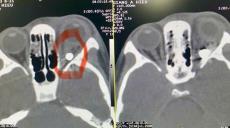

Điều trị thành công ca biến chứng võng mạc cấp tính cho một bệnh nhân người Đức

Giữa tháng 9/2025, bà Mirta Gayo Guerrero Eduardo Ortigueira Gómez, quốc tịch Đức, đang du lịch tại Việt Nam thì xuất hiện tình trạng giảm thị lực đột ngột mắt trái. Bệnh nhân đã tới khám tại Bệnh viện Mắt Trung ương trong tình trạng hoang mang, lo lắng. Sau khi thăm khám, hội chẩn và đánh giá các kết quả chẩn đoán hình ảnh, bệnh nhân được xác định xuất huyết dịch kính mắt trái, nghi có rách võng mạc và được chỉ định nhập viện điều trị ngay. BS.ThS Nguyễn Cảnh Thắng – Khoa Dịch kính Võng mạc là người trực tiếp điều trị ca bệnh này.